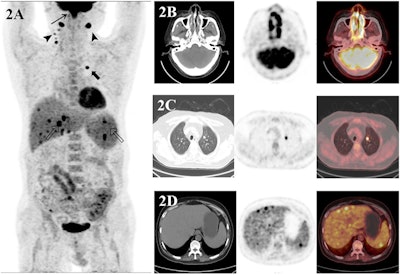

A 50-year-old man with recently diagnosed nasal-type NK/T-cell lymphoma underwent an F-18 FDG-PET/CT scan (A–D) for initial staging. Maximum-intensity-projection image (A) shows hypermetabolic lesions in both ethmoid sinus (thin arrow), both cervical lymphatic chains (arrowhead), left upper lung (thick arrow), liver, and spleen. Transaxial images show an F-18 FDG-avid mass in both ethmoid sinus (B). The scan shows intense F-18 FDG radiotracer uptake in left upper lung and uptake in the liver and spleen (CT showed no lesions), suggesting malignancy (C–D). Finally, after the PET/CT scan was done, the patient’s staging was changed from II to IV.Image courtesy of Heliyon